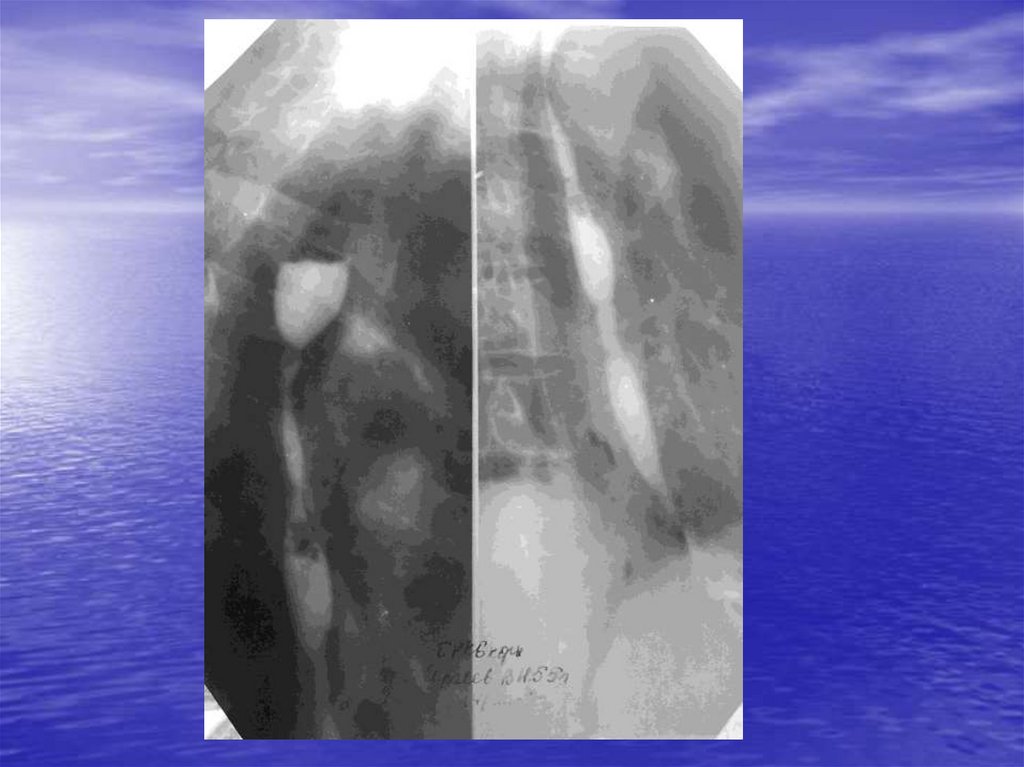

А) Перфорация стенки пищевода

В) Спонтанный разрыв пищевода

А) Ахалазия кардии